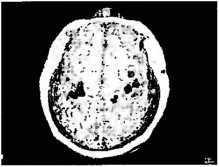

Магнитоэнцефалография (МЭГ): образ экспонируется на магнитно-резонансное отображение мозга пациента, у которого была ампутирована правая рука выше локтя.

Мозг рассматривается сверху. Правое полушарие показывает нормальную активацию корковых областей правой рухи (закрашено), лица (черная зона) и плеча (белая зона) в соответствии с картой Пенфилда. В левом полушарии нет активации, относящейся к правой отсутствующей рука, но теперь на згу область распространяется активность, идущая от лица и плеча

Чтобы напрямую проверить наши гипотезы «преобразования карты» и «перекреста проводов», мы использовали технику магнитоэнцефалографии, или МЭГ. Она показывает, какая часть мозга активируется при тактильном раздражении различных частей тела. Достаточно достоверно мы обнаружили, что у Виктора да и других пациентов с ампутированными конечностями) касание лица активирует не только область лица в мозгу, но также район руки в соответствии с картой Пенфилда (см. рис. 1.6). Это сильно отличается от картины, которую можно видеть у здорового мозга, — в данном случае касание лица активирует только лицевую область коры.